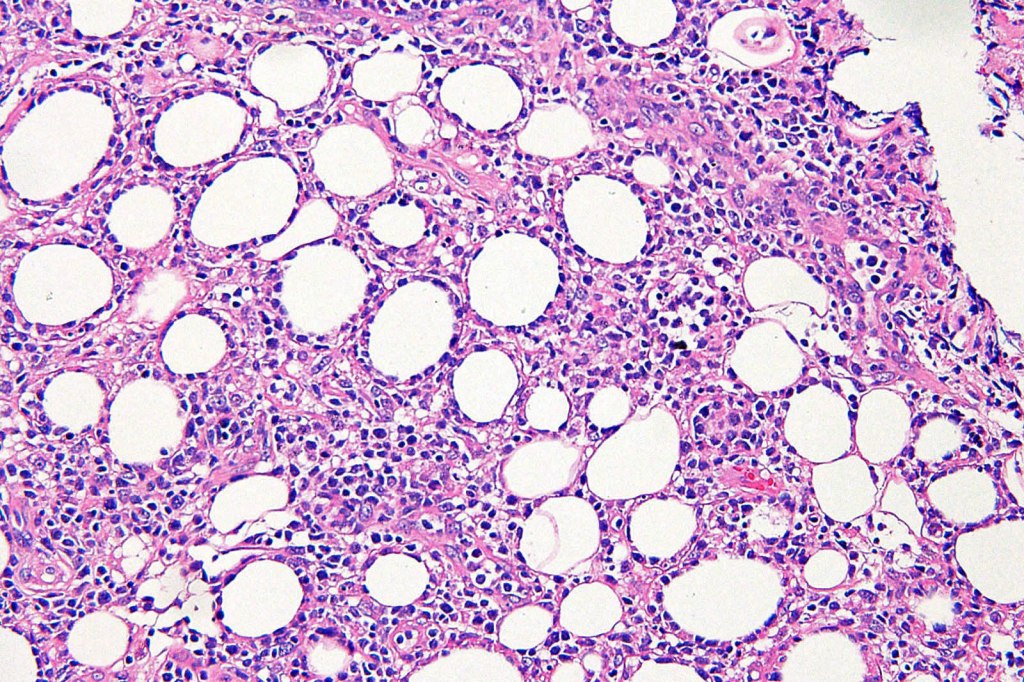

Histological features

•Dense infiltrate involving the lobules of the subcutaneous fat

•Epidermis & dermis are uninvolved

•Atypical lymphocytes with hyperchromatic nuclei & minimal cytoplasm

•Rimming of adipocytes

•Mitoses often abundant

•Fat necrosis with xanthoma cells & nuclear dust

•Variable hemophagocytosis (characteristic bean bag cells)